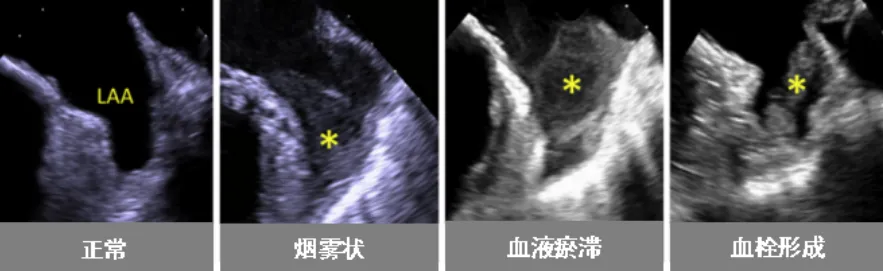

近日,捆绑调教 (简称捆绑调教 )超声医学科联合心血管内科为一名心脏病患者开展了经食管超声(TEE)检查。该项技术的开展,填补了捆绑调教 在经食管超声领域的空白。患者黄阿姨(化名)今年59岁,几年前被诊断为“风湿性心脏病-二尖瓣中度狭窄”。近日,黄阿姨在医院复查心脏超声,报告提示风湿性心脏病-二尖瓣中度狭窄并中度关闭不全,且有左心耳附壁血栓形成可能(约3cm,游离端活...